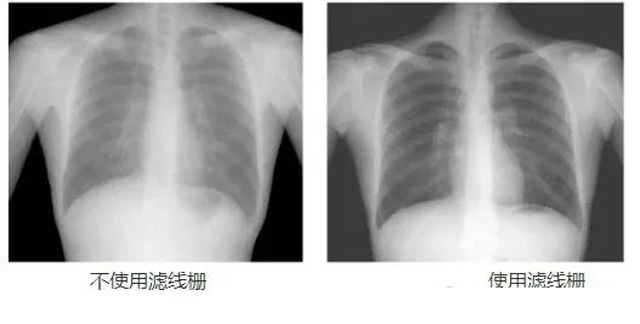

DR影像X射線在醫(yī)學(xué)檢查成像有著廣泛的使用。但是它的散射線影響成像質(zhì)量問題。濾線柵的發(fā)明使用很好的解決了這個(gè)問題,構(gòu)造簡單鉛條粗,密度和柵比規(guī)格單一,能減散射線但吸收較多原發(fā)射線。伴隨這醫(yī)療影像設(shè)備技術(shù)的發(fā)展,這個(gè)濾線柵的工藝制造技術(shù)有改進(jìn),鉛條變薄,柵密度和柵比有更多的選擇。特別是材料方面有新組合,填充物也依不同成像要求優(yōu)化。特別是移動DR這類型的DR設(shè)備的出現(xiàn),濾線柵也設(shè)計(jì)成立方便拆卸形的,方便使用。被照體情況決定是否使用,更好平衡成像質(zhì)量與射線劑量。